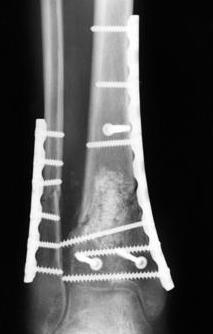

В приложении метафизарный перелом у ребёнка 14лет, с распространением линии перелома на зону роста.

3. стабилизировать наружный опорный комплекс голени и предотвратить вальгусную деформацию голеностопного сустава. Конечно, данная проблема не очень актуальна, или вовсе не актуальна для 43С1, но для повреждений типа 43С2,3, особенно в случаях, когда метафизарный дефект потребовал пластики, а пластину пришлось уложить по медиальной стороне - остеосинтез малоберцовой кости является крайне необходимым - привожу характерный пример.